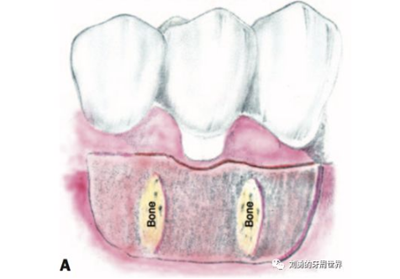

原因是:附著齦增寬的手術(shù),受區(qū)骨膜面積大,血供好,因此用偏薄的就可以,而對于根面覆蓋的手術(shù),受區(qū)外露根面沒有骨膜,血供差,因此取厚一點(diǎn)的,容易成活,對于牙槽嵴缺損的,建議取厚的,不是為了血供,而是為了更明顯的修復(fù)牙槽嵴的缺損。如下圖:

上面是附著齦增寬,因此取的薄一些。

上圖B23頰側(cè)牙槽嵴水平向塌陷明顯,為了增寬,取厚一點(diǎn)的齦瓣效果更好。